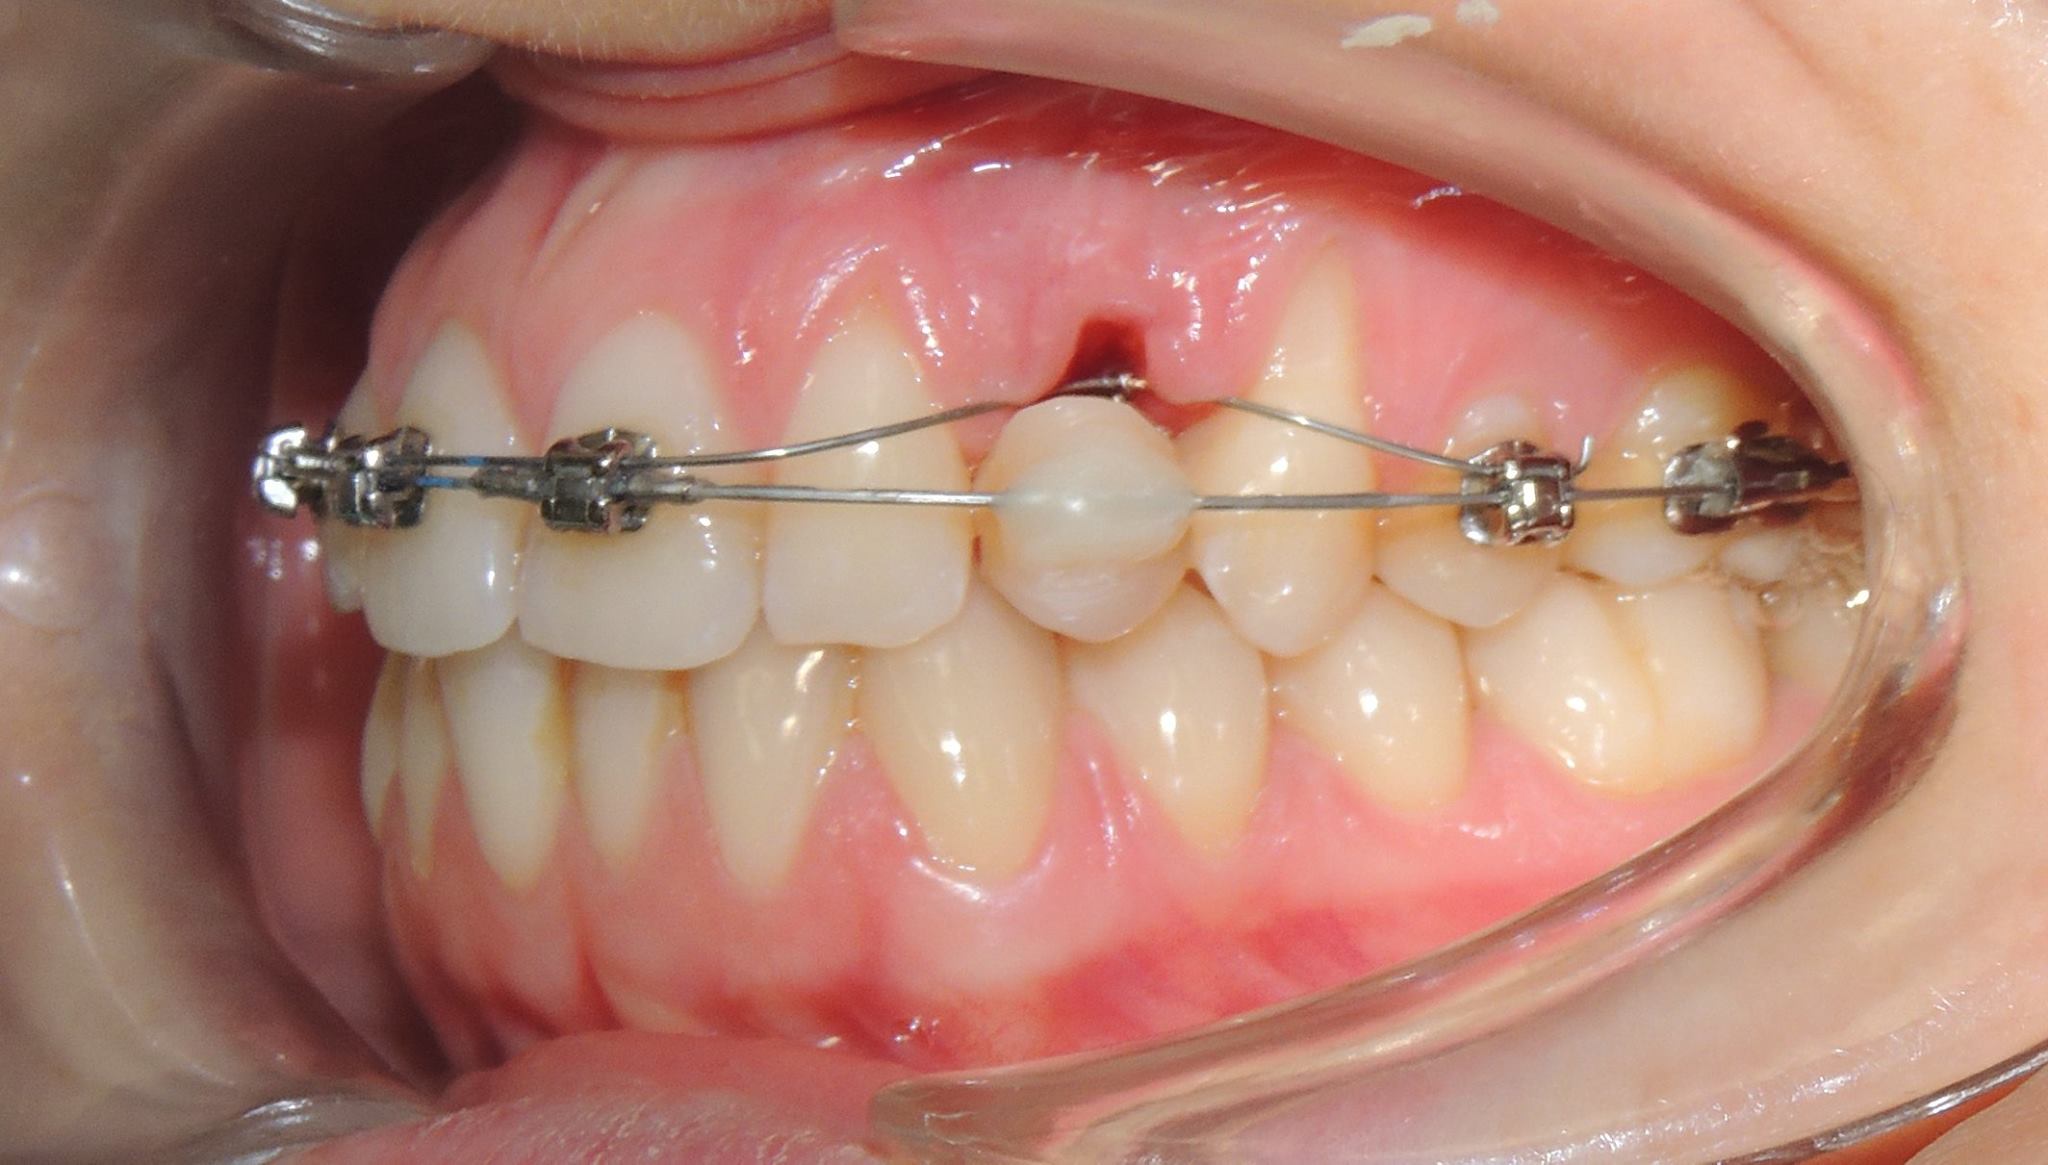

DRP + 2X2

17 dicembre 2016Disgiuntore Rapido del Palato e 2x2